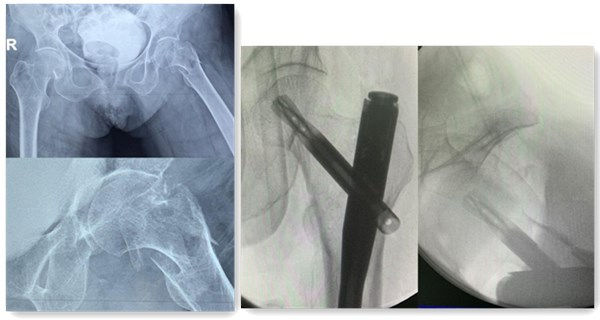

手术前X光影像、骨折移位明显 术中透视骨折复位及内固定

经过术前精心准备及预案,手术当天,麻醉满意,血压平稳,手术时间26分钟,出血50ml,3个分别2cm、2cm、1cm的切口就微创完成骨折复位、APFN内固定手术治疗。老太太平稳安返病房,家人和医护人员心里暂时放下一颗大石。